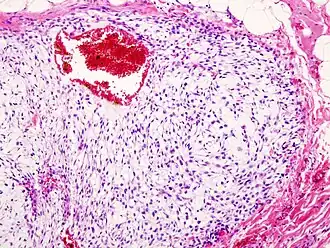

Image de Chondrosarcome de la cage thoracique. Coloration à l'hématoxyline et à l'éosine.

Le chondrosarcome est une tumeur maligne primitive osseuse avec des cellules tumorales présentant une matrice cartilagineuse hyaline[1]. Le chondrosarcome est la deuxième tumeur osseuse maligne en termes de fréquence, derrière l'ostéosarcome.